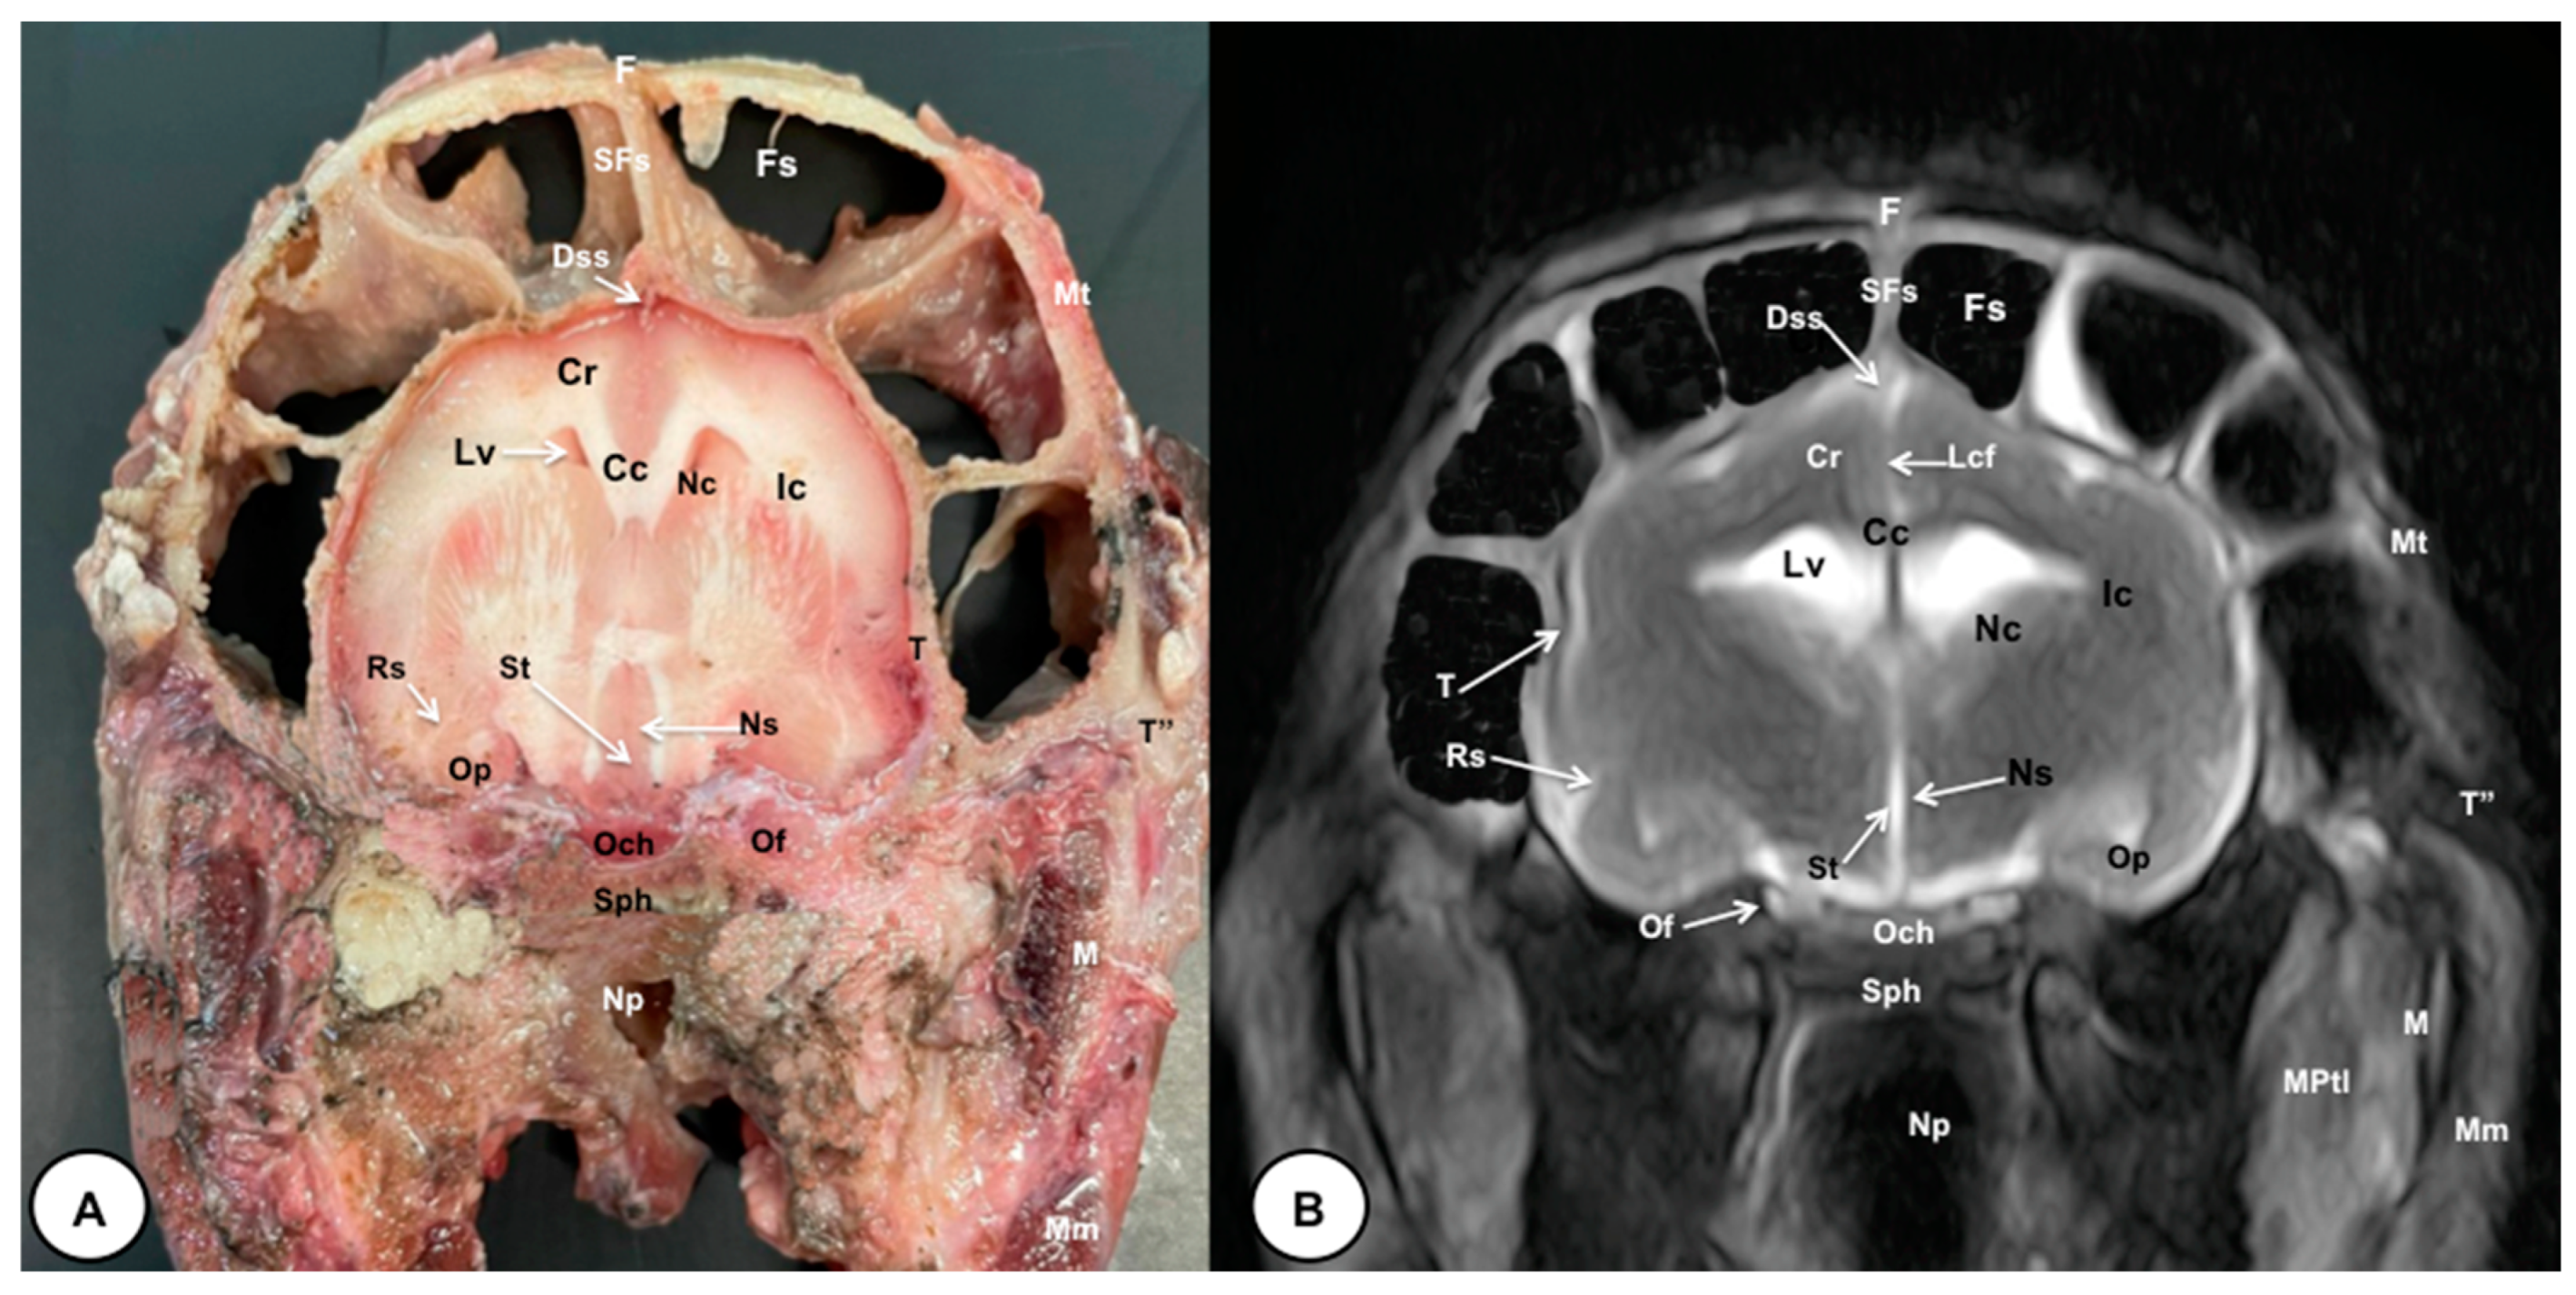

3.1. Anatomical Cross-Sections

3.2. Magnetic Resonance Imaging (MRI)